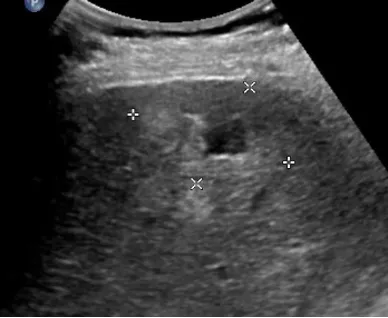

肝脓肿

● 定义:肝脓肿是肝脏的化脓性炎症,可由细菌、真菌或阿米巴原虫等感染引起。病理过程通常包括炎症浸润期、脓肿形成期和脓肿吸收期。

● 超声表现:

1.肝内单个或多个占位性病变。

2.早期呈低回声,边界不清,血流丰富。

3.脓液形成后,呈液性暗区,壁厚薄不均,内壁不平整,内透声差,可见絮状回声,有些可见分层。

4.肝脓肿进一步发展,内透声好,如肝囊肿,但壁厚薄不均。

5.后方结构(后壁)回声增强。